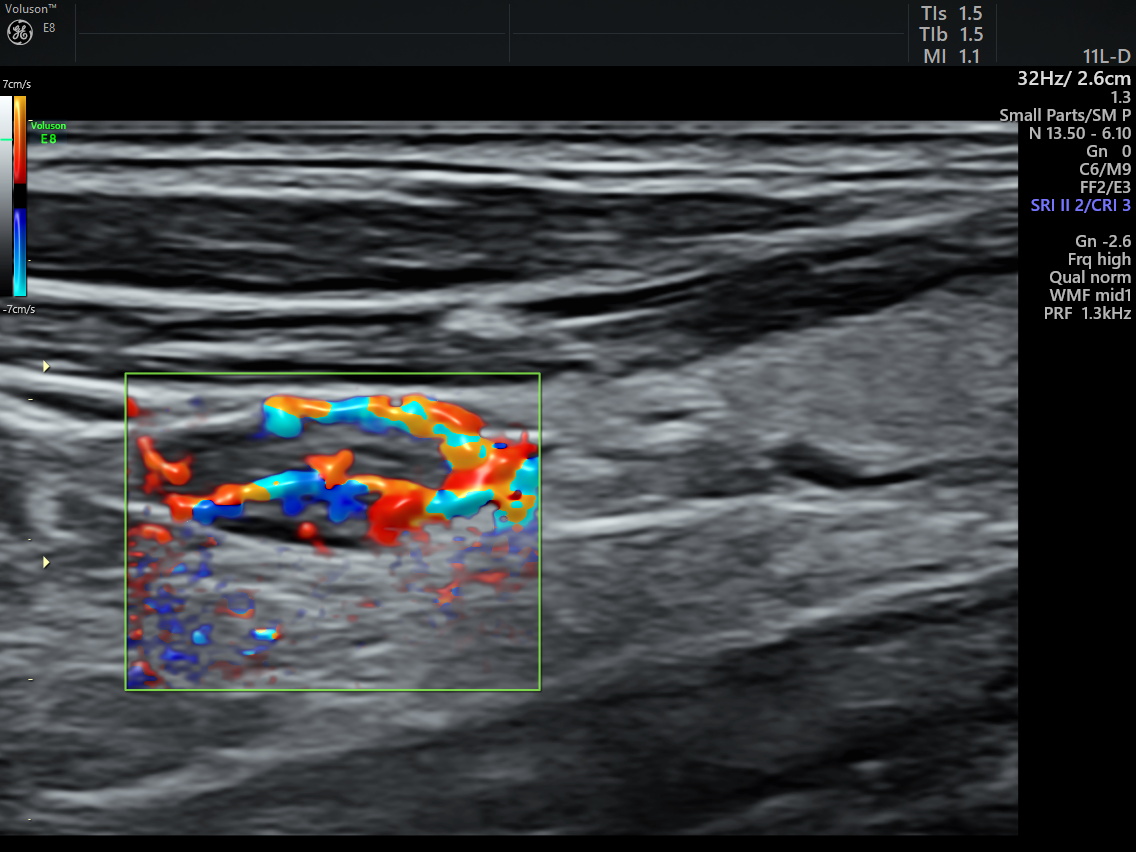

治疗前病灶血流丰富 治疗后病灶血流消失

术中,在高频超声的实时引导下,通过穿刺针水隔离病灶部位与周围组织器官,通过精准导航在完整消融病灶的同时,最大程度避免了对周围正常组织的损伤,仅用时数分钟就完成了整个治疗。术中术后患者未出现声音嘶哑及出血等并发症,术后即刻超声造影显示病灶区无增强,提示消融完全,在住院19小时后患者顺利出院。出院前复查甲状旁腺素12.4pg/ml,呈“断崖”式下降,血钙2.46mmol/L,标志着腺瘤病灶被完全灭活,甲状旁腺功能异常得到纠正,血钙恢复到正常水平,治疗效果显著。

消融过程 消融后造影病灶无增强